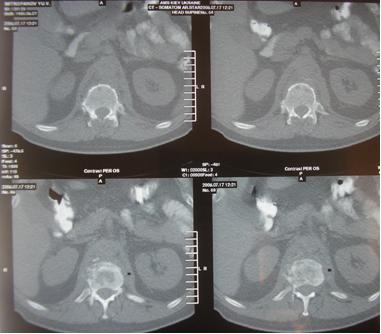

- КТ (компьютерная томография) - так же позволяет исключить паравертебральный или спинальный эпидуральные абсцессы, более информативна для остеомиелита позвоночника, который часто сопровождает спинальный эпидуральный абсцесс;

Компьютерная томография (КТ):

Компьютерная томография делает изображение более наглядным, представляя на экране монитора в виде трехмерной фигуры, и позволяет точнее оценить размеры абсцесса.